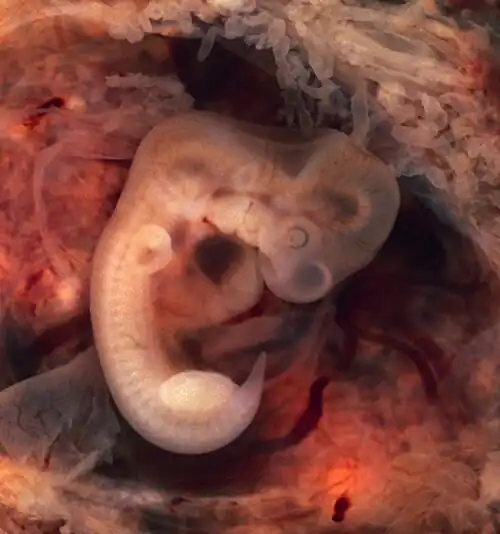

Author: Ed Uthman

Image of a human embryo at 7th weeks of gestational age. doi: 10.15347/WJM/2014.007